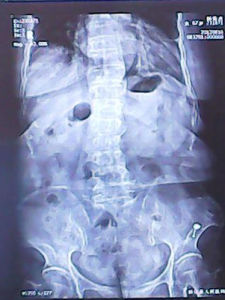

3、X線攝片有骨折。

4、影像學檢查有助於明確診斷,缺點損傷部位,類型和移位情況,X線攝片是首選的檢查方法,老年人感覺遲鈍,胸腰段脊柱骨折往往主訴為下腰痛,單純腰椎攝片會遺漏下胸椎骨折,因此必須註明攝片部位包括下胸椎(T10—12)在內,通常要拍攝正側位兩張片子,必要時加拍斜位片,在斜位片上則可以看到有無椎弓峽部骨折。由於頸椎前方半頭尾是一種隱匿性損傷,沒有明顯的骨折,普通的X線攝片檢查時很容易疏忽掉而難以診斷。

(4)下一節椎體前上方有微小突起表示有輕微的脊椎壓縮性骨折。X線檢查有其局限性,它不能顯示出椎管內受壓情況,凡有中柱損傷或有神經症狀者均須作CT檢查。CT檢查可以顯示出椎體的骨折情況,還可顯示出有無碎骨片突出於椎管內,並可計算出椎管的前後徑與橫徑損失了多少,CT片不能顯示出脊髓損傷情況,為此必要時應作MRI檢查,在MRI片上可以看到椎體骨折出血所致的信號改變和前方的血腫,還可看到因脊髓損傷所表現出的異常高信號。

多為傳遞暴力所造成,如高處跳下,部分由於直接暴力的打擊所致。根據暴力和脊柱所處位置的不同,可分為過伸性損傷和過屈性損傷。過伸性損傷較少見,常引起脊椎後方附屬檔案骨折。過屈性損傷占多數,最易形成椎體壓縮性骨折,或伴附屬檔案骨折。影像學表現

1.椎體骨折最常見的是椎體壓縮骨折,好發於胸11,12椎,腰1,2椎。受損部位多涉及椎體的上部,尤以前方為甚。明顯的壓縮骨折在正位片上顯示為椎體上部的塌陷,骨松質因壓縮而增密,骨小梁排列紊亂。在側位片上,壓損的椎體呈楔形改變,椎體的前方變狹,後方較寬,上緣向下傾斜,骨皮質有折斷和凹陷現象。椎體上面的椎間隙和上面一個椎體的下緣多顯示正常。椎體骨折亦可沒有壓縮而在椎體邊緣出現斜行或橫行骨折線或呈小片骨撕裂等。2.椎弓和關節突骨折椎弓骨折最常見於下腰段,以腰椎斜位片觀察為佳。關節突骨折可見於過伸性或過屈性外傷,一般以腰段和頸段較多。

3.棘突和橫突骨折多見於突起較長者,如腰椎的橫突和下頸椎的棘突。可合併發生於椎體骨折,亦可單獨出現於肌肉韌帶的強烈撕脫,骨折線常呈橫斷或斜形。